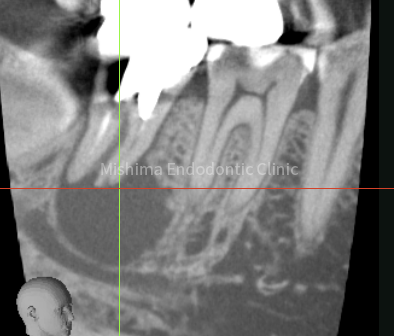

| 治療内容 | 既根管治療歯で比較的大きな根尖病変を認めた。根管治療は貼薬無しで即日根管充填。 術後、根尖透過像は消失し経過は良好。 |